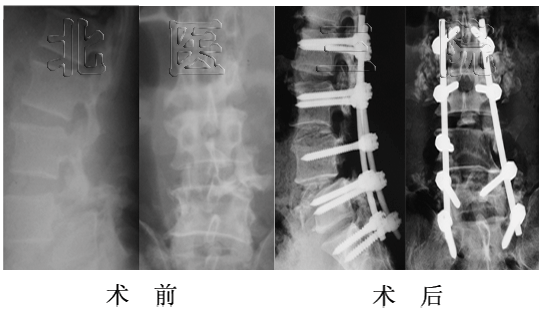

女性,17岁,胸腰段结核性后凸,术前后凸角度130o,经后路矫形术后仅剩37o,矫正率71.5%